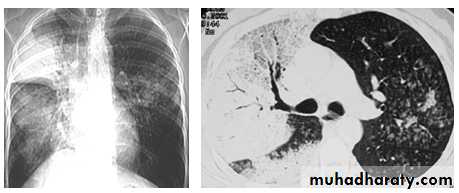

Miliary Tuberculosis. A cone-down view of a frontal radiograph demonstrates innumerable micronodular opacities characteristic of micronodular (miliary)

interstitial disease.

Transbronchial biopsy demonstrated caseating granulomas containing acid-fast bacilli.

Miliary TB

a frontal radiograph demonstrates innumerable micronodular opacities characteristic of micronodular (miliary) interstitial disease. Transbronchial biopsy demonstrated caseating granulomas containing acid-fast bacilli.Tuberculoma